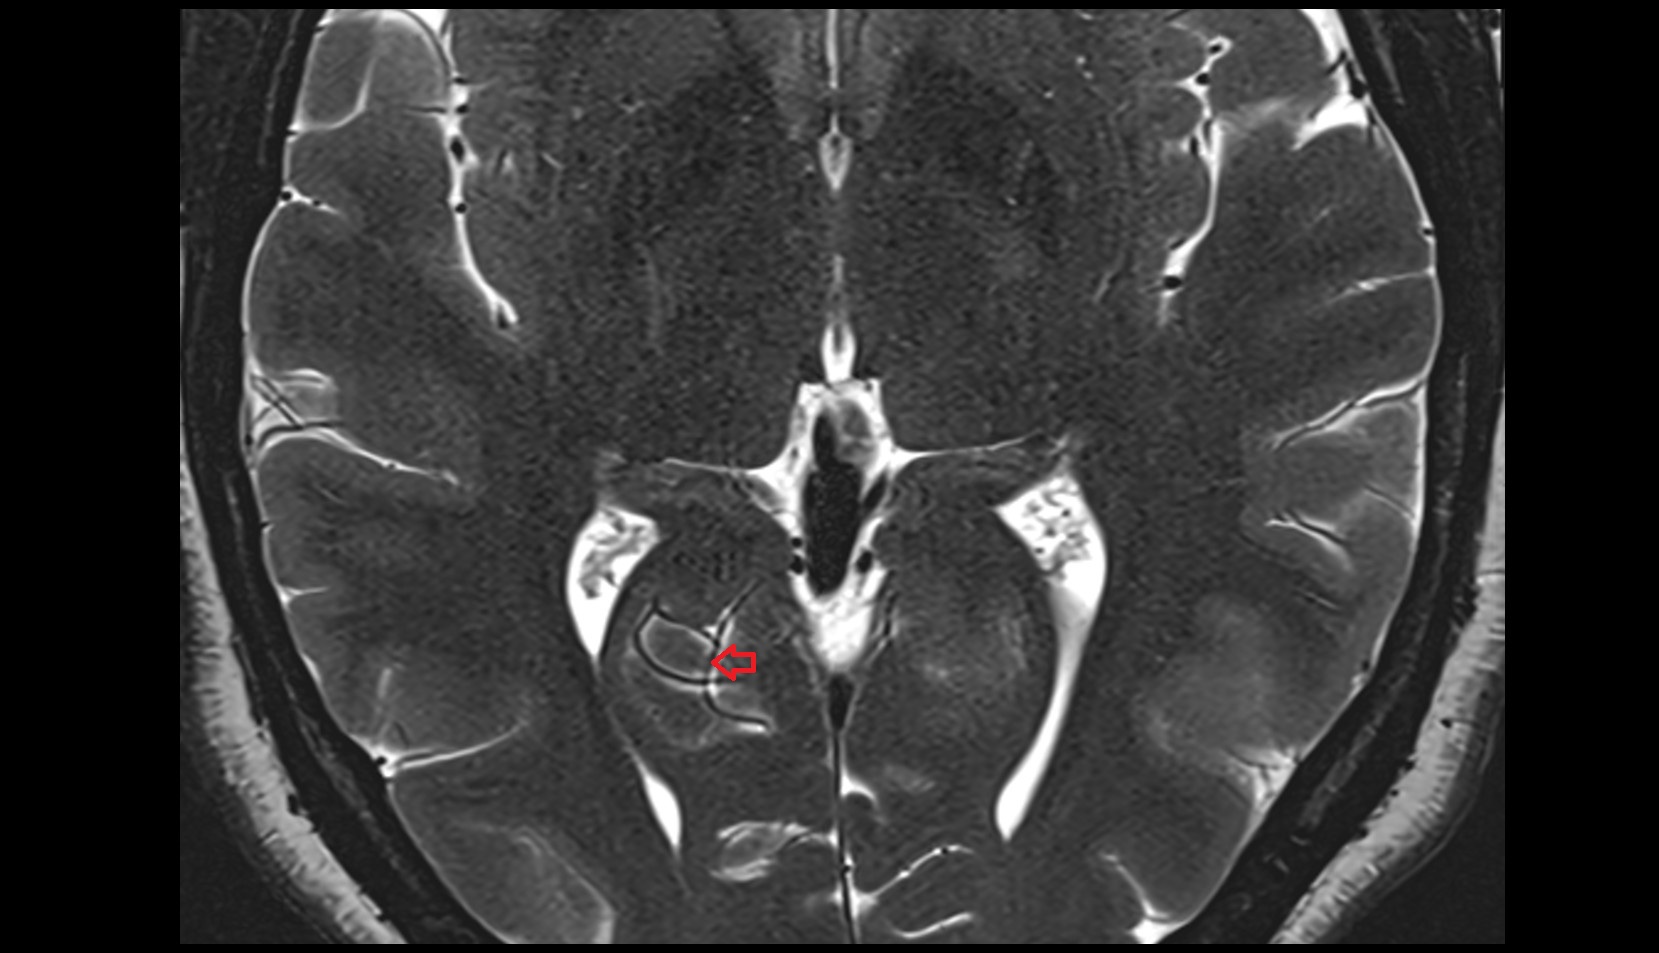

- Choroid fissure

- Superior opening of cerebral aqueduct